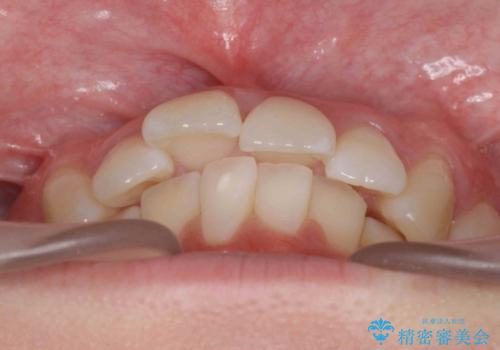

歯を抜かないで出っ歯を治したい

- 前歯が出ていることを主訴に来院。

歯を抜かずにマウスピース矯正をご希望でした。

歯と歯の間をわずかに削り、歯並びを少し横に拡大して並べました。

奥にすき間がなかったため後ろには下げていません。

沢山ひっこめるには4本抜歯でワイヤーの選択肢もありましたが、抜かないでできる範囲をご希望されました。

とがった形の歯列を整えるだけでもだいぶ印象は変わると思います。

今回歯列を広げた結果、上顎犬歯の歯肉は多少退縮しています。